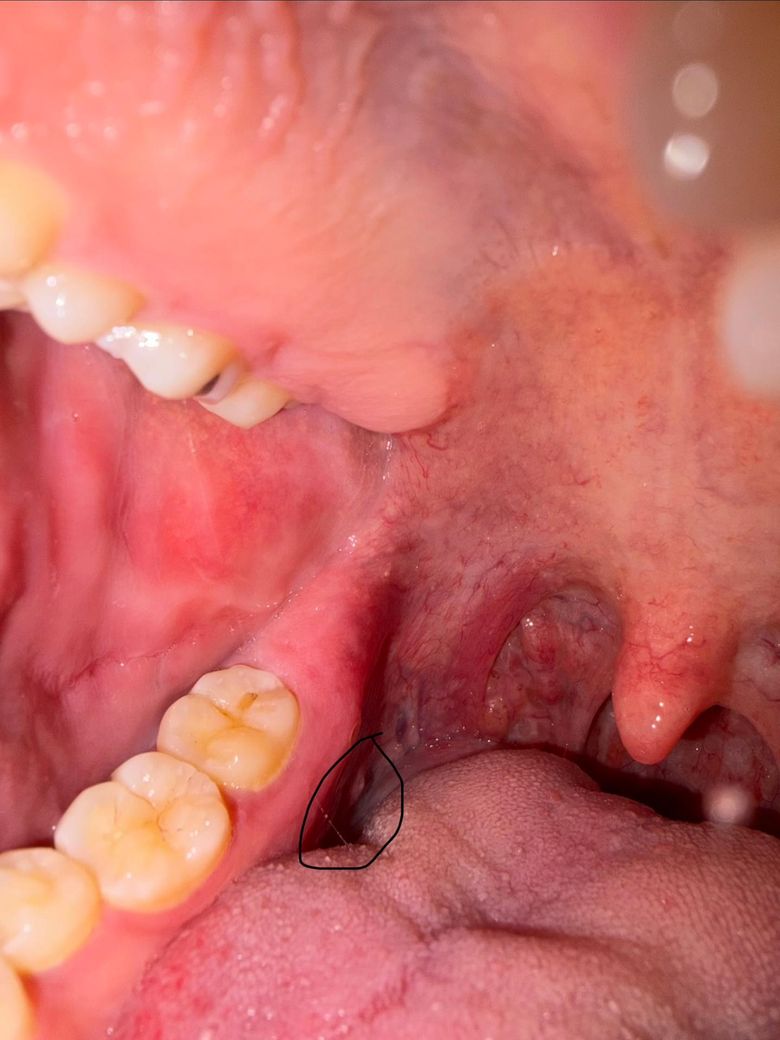

오른쪽 어금니 뒷 쪽과 혓바닥 뒷 부분 사이에 있는 옆 쪽의 잇몸이 이틀 전인가 부터 아프더라고요

워낙 뒤 쪽에 있고 안 쪽에 있어서 폰 후레쉬로 비춰도 자세히는 확인이 안되는 위치라 정확히는 저도 확인이 안되고요

• 1번 째 사진